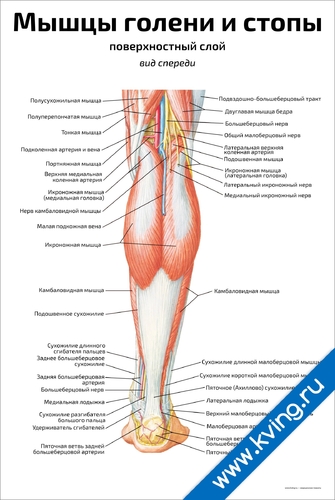

Анатомия подошвенной мышцы голени: подробное рассмотрение